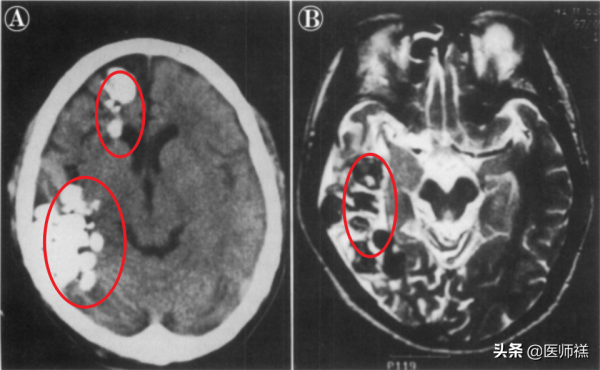

這位患者自述經常腦部經常劇烈頭痛、偶犯癲癇、有時候手腳不聽使喚,腦部核磁共振檢查結果顯示右半球的顳枕葉和額葉有多個環狀增強,或許你覺得他是腦中風的表現。

- 如果定值在腦部就會引發腦部組織出現水腫、囊腫病變,侵害神經影響感覺障礙,重者形成癱瘓不能自理,更重者引發患者死亡。